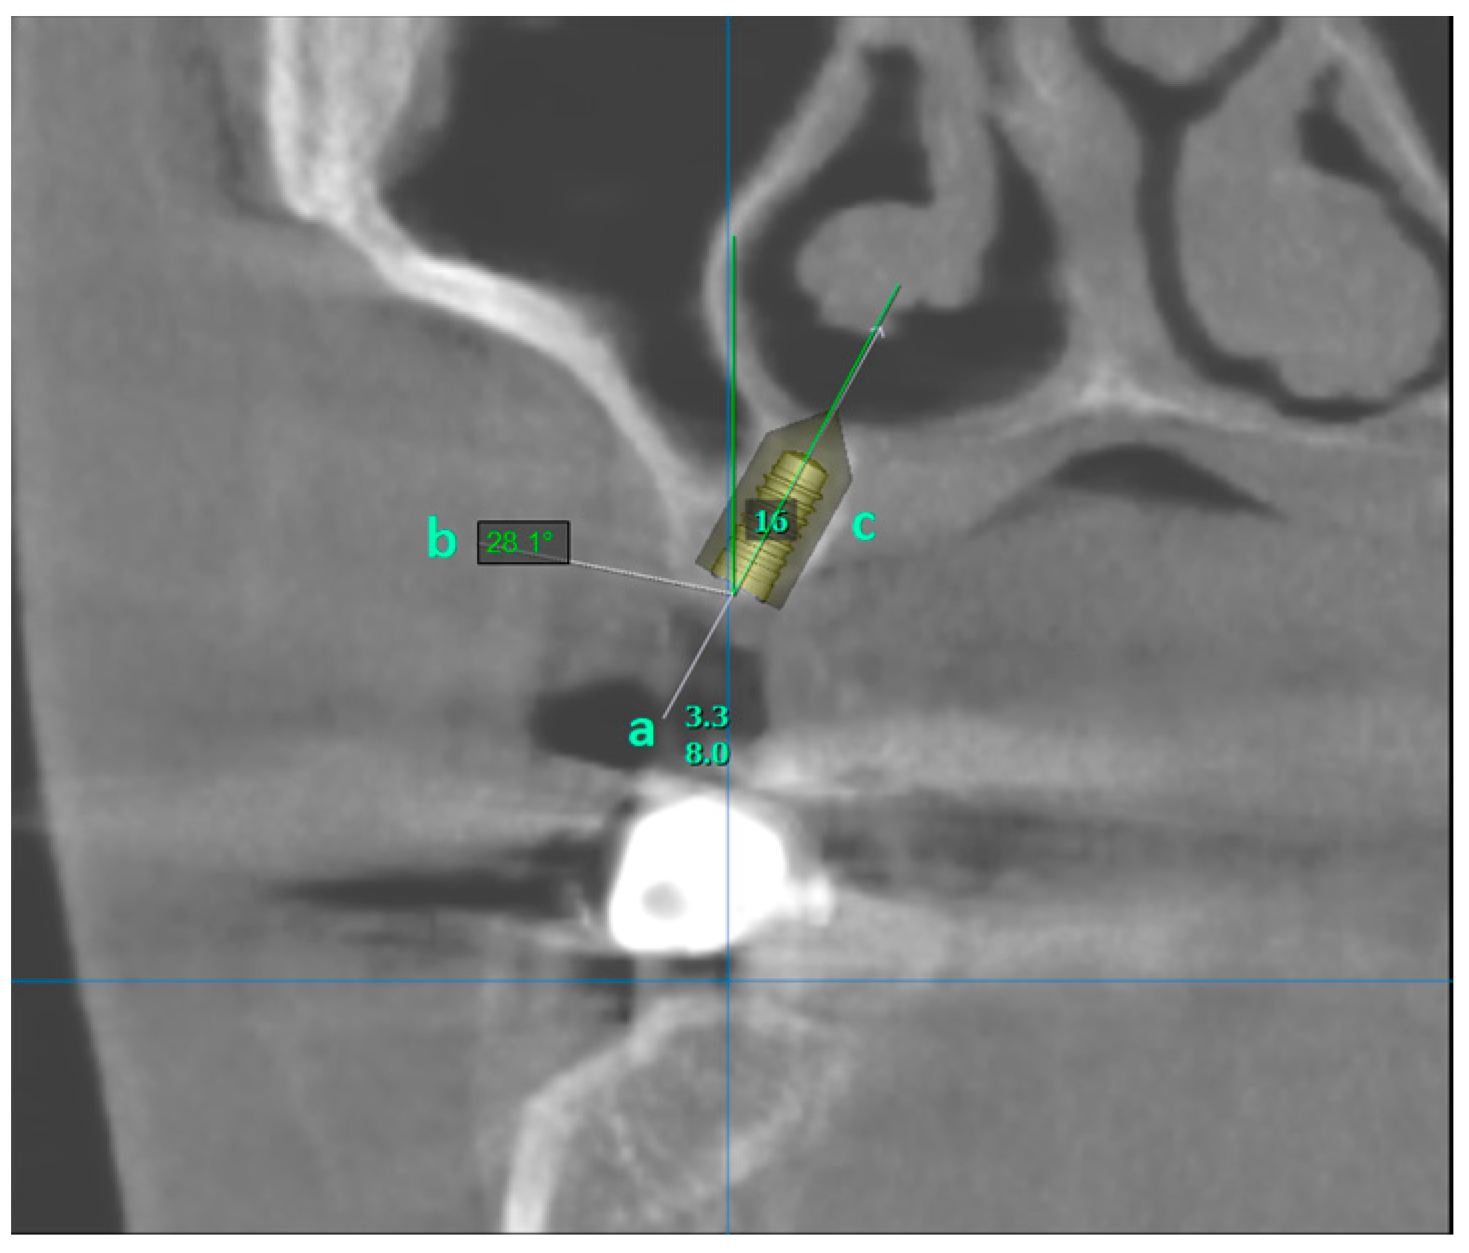

Avoiding Sinus Floor Elevation by Placing a Palatally Angled Implant: A Morphological Study Using Cross-Sectional Analysis Determined by CBCT

Kaya, D.I.; Şatır, S.; Öztaş, B.; Yıldırım, H. Avoiding Sinus Floor Elevation by Placing a Palatally Angled Implant: A Morphological Study Using Cross-Sectional Analysis Determined by CBCT. Diagnostics 2024, 14, 1242. https://doi.org/10.3390/diagnostics14121242